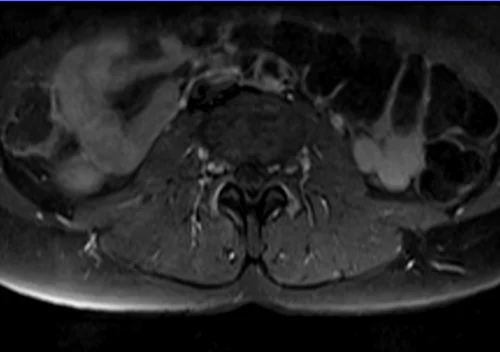

L plexus mri T1 fat saturated post contrast axial images